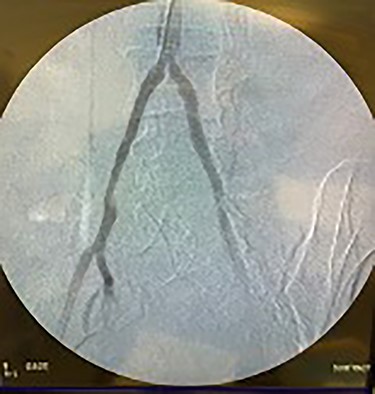

Catheter arteriogram results showed significant occlusion of the left iliac artery (Figs 3 and 4), the right iliac artery (Fig. 1), as well as the distal abdominal aorta (Fig. 2). There were numerous collateral vessels noted, indicating the presence of long-standing proximal stenosis (Fig. 1). The decision was made to use angioplasty to help widen the areas of stenosis. An 8 mm × 40 mm Passeo balloon was advanced from the right femoral artery into the left iliac artery (Fig. 7) and insufflated to 6 mmHg (Fig. 6). The balloon was allowed to remain expanded for 1 min and then was deflated. Next, the distal aorta was repaired in a similar fashion. The balloon was advanced into the distal aorta from the right femoral access and insufflated to 12 mmHg (Fig. 8). The balloon was allowed to remain expanded for 90 s.

Fluoroscopy of bilateral iliac arteries showing significant arterial disease.